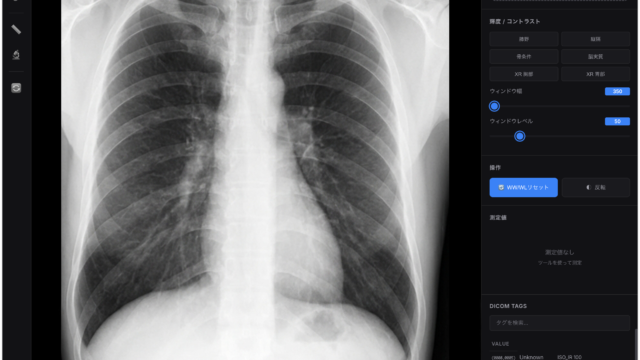

近年の国家試験は、画像問題の比率が高まっています。 「CT画像を見ても、どこの臓器か分からない…」 そんな状態で試験に挑むのは無謀です。

教科書の綺麗な解剖図を眺めているときは「分かった気」になります。 しかし、実際のCT画像はモノクロで、境界も曖昧です。

3. 「正常」を知らずして「異常」は語れない

画像問題の多くは「異常所見」を問うものですが、正常解剖が頭に入っていなければ、異常に気づくことはできません。 病変を探す前に、まずは「正常な血管の走行」や「正常な臓器の形」を完璧にしてください。

正常を知り尽くした者だけが、画像の中の「違和感(病変)」に瞬時に反応できるのです。

CT画像が、ただの白黒の模様から、意味のある地図に変わる瞬間が必ず来ますよ!